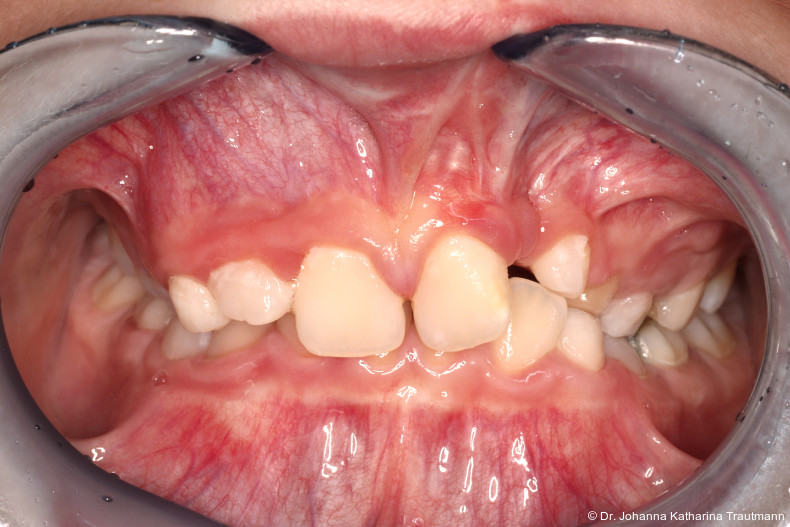

Auch im Rahmen der Zertifizierung durch das German Board of Orthodontics and Orofacial Orthopedics (GBO) wird dieser Aspekt gezielt hervorgehoben: Bewerberinnen und Bewerber sind aufgefordert, Fälle vorzustellen, die eine enge Kooperation verschiedener Fachdisziplinen dokumentieren und somit die Vielschichtigkeit und Tiefe der kieferorthopädischen Behandlungsmethoden aufzeigen. Hierdurch wird deutlich, dass die Kieferorthopädie sich nicht allein auf fachspezifische zahnmedizinische Themen fokussiert, sondern einen wesentlichen Beitrag zur allgemeinen interdisziplinären medizinischen Versorgung leistet. Der nachfolgende Fallbericht zu einem Patienten mit ein seitiger Lippen-Kiefer-GaumenSpalte zeigt exemplarisch, wie bei einem um fangreichen Behandlungs fall die Kieferorthopädie als zentrales Bindeglied zwischen den Disziplinen fungiert und damit maßgeblich zur funktionel len und ästhetischen Rehabilitation des Patienten beigetragen hat. Erstvorstellung Der Patient stellte sich im Alter von 11,5 Jahren auf Anraten einer niedergelassenen Kollegin in der Poliklinik für Kieferorthopädie der Universitätsmedizin Göttingen vor. Hauptanliegen war die Beurteilung einer möglichen Durch bruchsproblematik sowie die Indikationsstellung einer sekundären Osteoplastik im Rahmen einer einseitigen Lippen-Kiefer-Gaumen-Spalte.

Allgemeinanamnestisch berichtete der Patient über eine eingeschränkte Nasenatmung und nächtliches Schnarchen. Ein bestehendes Asthma bronchiale wurde medikamentös durch ein corticoides Bedarfsspray kontrolliert. Der CMD Kurzcheck nach Ahlers und Jakstat1 zeigte keine Auffälligkeiten. Extraoral fiel ein konvexes Profil mit ausgeprägter Kinnprominenz sowie enface der linksseitige Narbenzug mit charakteristisch abgeflachtem Nasenflügel auf.

Das Fernröntgenseitenbild zeigte eine skelettale Klasse IIAnomalie mit einem Wits von 5,6 mm, bei einer tiefen Konfiguration (ML NL = 16,5°) mit bialveolär retrudierten Fronten (OK1NA = 5,9°; UK1NB = 10,4°), was sich auch in der Modellanalyse widerspiegelte. Hier zeigte sich zudem ein schmaler Oberkiefer mit multiplen Kippungen und Rotationen in der Front, einem hypoplastischem 22 sowie einer Mesialwanderung des 16. Des Weiteren zeigte sich eine asymmetrische Bisslage mit 1 PB distal rechts und ½ PB distal links bei einem Overjet von 2,5 mm sowie einem Overbite von 5 mm. Während im Unterkiefer bereits die zweite Zahnwechsel phase begonnen hatte, zeigte sich im Oberkiefer noch kein Wechsel in den Stützzonen. Gerade bei Patienten mit Spaltbildungen ist eine engmaschige Überwachung des Durchbruchs der oberen Eckzähne essenziell. Während bei der Allgemeinbevölkerung die Prävalenz von verlagerten Eckzähnen bei ca. 2,8 Prozent liegt2, ist diese bei Patienten mit Lippen-Kiefer-Gaumen-Spalten um den Faktor 10 erhöht.3, 4 Als klassische Risikofaktoren gelten zudem Platzmangel, transversale Enge aber auch Fehlstellungen, Nichtanlagen oder Hypoplasien der zweiten Schneidezähne. Diese übernehmen normalerweise die Funktion der Leitschiene für den S-förmigen Durchbruch der Eckzähne. Im vorliegenden Patientenfall kommen also mehrere Risikofaktoren für eine Verlagerung zusammen, was die rechtzeitige Diagnostik zur Abklärung einer Durchbruchsproblematik rechtfertigt. Da im Spaltbereich auch zusätzlich ein ausgeprägtes Knochendefizit vorliegen könnte, sollte auch immer die Option einer sekundären Osteoplastik abgewogen werden, deren Indikation und Timing optimal zum Durchbruch der Canini angepasst werden sollte.5